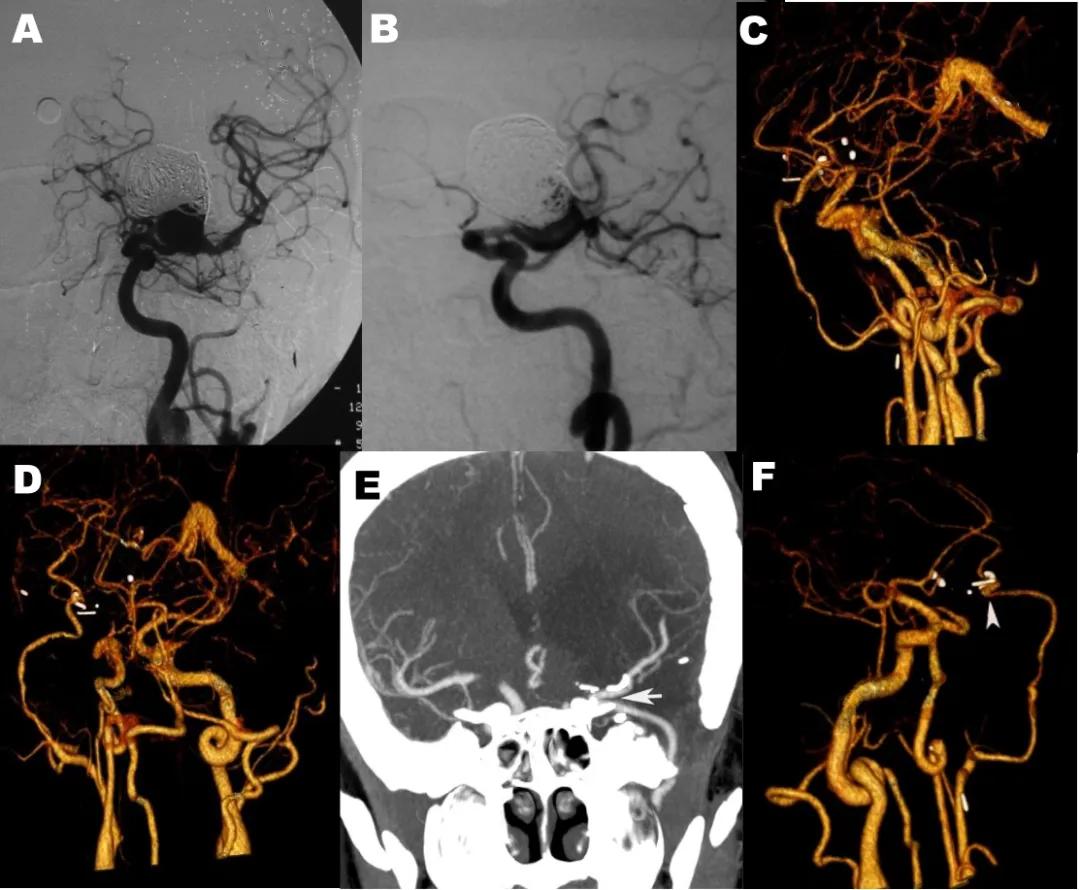

一例男性,27岁,左侧大脑中动脉巨大动脉瘤,血管内栓塞治疗7次,头痛言语困难10个月。用颌内动脉-M2段搭桥的患者,术后9年(2019年10月13日)造影复查显示动脉瘤消失,搭桥血管通畅,患者已恢复正常生活,见图5。

图5 A和B,左侧颈动脉造影正侧位像显示左侧大脑中动脉动脉瘤栓塞治疗复发;C和D颌内动脉搭桥术后CTA正侧位像显示动脉瘤消失,颌内动脉与大脑中动脉搭桥通畅;E和F术后九年随访,E,CTA三维正位,F,侧位血管影像显示颌内动脉搭桥通畅,动脉瘤消失。